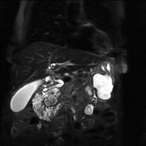

Massive retroperitoneal dedifferentiated liposarcoma in a young patient

Fernando X Moyon and others

Journal of Surgical Case Reports, Volume 2018, Issue 10, October 2018, rjy272, https://doi.org/10.1093/jscr/rjy272